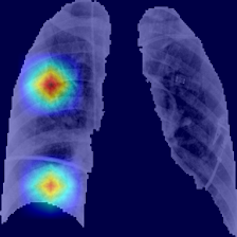

Se recurre a esta técnica de imagen porque, debido a la afectación primaria del sistema respiratorio, la infección por SARS-CoV-2 deja evidencias radiológicas de neumonía visibles bajo los rayos X. Concretamente, la neumonía asociada a la covid-19 produce sombras en los pulmones conocidas como opacidad de vidrio esmerilado. Estas opacidades suelen aparecer con una distribución periférica o posterior, principalmente en los lóbulos inferiores y con menos frecuencia en el lóbulo medio derecho.

La herramienta proporciona un método objetivo complementario, mínimamente invasivo para el diagnóstico, que evalúa el grado de afectación por la covid-19. Alcanza una precisión por encima del 90%, superior incluso a la alcanzada por los expertos en radiología. Además, proporciona evidencias con capacidad diagnóstica en estadios incipientes de la enfermedad (los cinco primeros días).

La herramienta también identifica el área de mayor afectación y permite cuantificar de forma objetiva lo extenso de la infección. Sin olvidar que reduce significativamente el tiempo dedicado por los expertos en radiología a la evaluación de cada paciente.